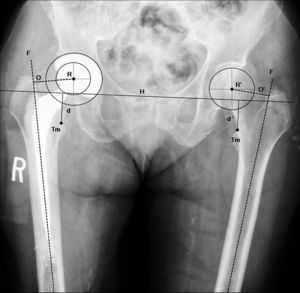

El plantillado acetabular comienza con el trazado de una línea horizontal de referencia para determinar la inclinación correcta del componente acetabular. En la gran mayoría de los casos puede trazarse esta línea a través de los vértices inferiores de ambas imágenes en lágrima28 (fig. 1). Si las imágenes en lágrima no fueran claramente visibles, pueden utilizarse los vértices inferiores de las articulaciones sacroilíacas. Los vértices inferiores de las tuberosidades isquiáticas están frecuentemente distorsionados por rotaciones pélvicas, fracturas previas o variaciones anatómicas.

Si ambos cotilos tienen forma y tamaño similar, el plantillado del componente acetabular puede realizarse en el cotilo de la cadera no fracturada. El plan comienza marcando el borde acetabular superoexterno, la línea ilioisquiática y la imagen en lágrima. La visualización del margen anterior y posterior del cotilo puede guiar al cirujano en la determinación correcta de la anteversión acetabular durante la cirugía.

Posteriormente, se determinan la posición y el tamaño del componente acetabular utilizando las plantillas con magnificación adecuada. Mediante la superposición de las plantillas del componente acetabular se busca aquel tamaño que cumpla con las siguientes condiciones: copa con abducción aproximada de 45°, borde medial de ésta, aproximada a la línea ilioisquiática, borde inferior aproximado a la línea horizontal de referencia interlagrimal con el que se obtenga una máxima cobertura lateral ósea con mínima remoción de hueso esclerótico subcondral (fig. 2A). Tras la selección del tamaño y posición del componente acetabular se marca en la radiografía el centro de rotación y el perfil de la copa.

Plantillado del componente acetabular. A) La imagen muestra un componente acetabular de tamaño y posición adecuados. B) Imagen que muestra la utilidad de la distancia (d) entre el borde inferomedial del componente acetabular y el vértice inferior de la imagen en lágrima para determinar la inclinación acetabular precisa. La distancia (d) en una copa con una inclinación correcta (45°) aumenta a una distancia (d’) con el incremento de la inclinación del componente acetabular (A’ a 60° de inclinación). Por otra parte, con el incremento de la inclinación de la copa acetabular, reduciremos la cobertura lateral de la copa, que se ve reflejado en la menor distancia entre el vértice superior de la copa y el borde acetabular superoexterno. a: borde acetabular superoexterno; A: componente acetabular con inclinación correcta; A’: componente acetabular verticalizado; b: línea ilioisquiática; c: imagen en lágrima; d: distancia del componente acetabular correcto; d’: distancia del componente acetabular verticalizado; e: distancia entre el vértice superior de la copa y el borde acetabular superoexterno; H: línea horizontal de referencia; R: centro de rotación del componente acetabular.

Para lograr reproducir intraoperatoriamente la inclinación del componente acetabular planificado deben tomarse 2 medidas radiológicas con la regla magnificada. La primera es la distancia entre el vértice inferior de la copa dibujada y la imagen en lágrima (fig. 2B). Esta distancia suele ser corta (5–10mm) y muy sensible a los cambios de inclinación de la copa. La segunda medida es la distancia entre el vértice superior de la copa acetabular y el borde acetabular superoexterno.

Imagen radiográfica anteroposterior de pelvis que muestra una artroplastia total de cadera por fractura (paciente de la fig. 1) implantada tras la realización de la planificación preoperatoria (tabla 1). Se comprueba la correcta posición de los implantes y la restauración anatómica de la biomecánica de la cadera fracturada (centro de rotación, offset [O=O’] y longitud del miembro [d=d’]). d: distancia vertical desde la línea de referencia al ángulo proximal del trocánter menor de la cadera operada; d’: distancia normal; F: eje de la diáfisis femoral; H: línea de referencia horizontal entre ambas imágenes en lágrima; O: offset de la cadera operada; O’: offset normal; R: centro de rotación de la artroplastia; R’: centro de rotación de la cadera normal; Tm: trocánter menor.